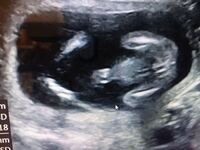

男の子のエコー写真 男の子のシンボルが見えやすいエコー写真を集めてみました! ぜひ参考にしてみてくださいね☆ 17週の男の子のエコー写真 左側がお尻、上下に足が見え、その間にシンボルが見えます。 19週の男の子のエコー写真17週0日(17w0d・男の子)|Ayako さん(32歳) エコー写真撮影時のエピソード: 戌の日の安産祈願に行った時に周りの妊婦さんがかなりお腹が大きかったのに、私はお腹がなかなか大きくならずに心配していましたが、エコーの赤ちゃんはきちんと大きくなっていて安心できました。性別判定のため17週で4Dエコーを受けてきました!17w6d時点 何故4Dエコーを受けようと思ったのか 安定期に入ってから性別が気になり出しました。辛かったつわりは絶賛継続中です。 ただ以前ほどではなく布団の中での生活からは抜け出せています。

17週のときのエコーです!これは男の子のシンボ 写真多数週数別女の子のエコーの見分け方! 妊娠17週目エコー写真・胎児の大きさ・胎動や性 17週 性別 男の子 エコー エコー写真の性別判断 妊娠17週目(17w0d~6d)のエコー写真とエピ男の子のエコー写真の 17週のエコーです。性別は男の子で確定でしょうか??? 早く分かれば名前決めたりしたいなあ どう思われますか?皆さんのエコーが見たいです 6月3日 お気に入り 妊娠17週目 性別 男の子 名前 エコー choco (3歳8ヶ月) コメント 6月 3男の子のエコー写真 男の子のシンボルが見えやすいエコー写真を集めてみました! ぜひ参考にしてみてくださいね☆ 17週の男の子のエコー写真 左側がお尻、上下に足が見え、その間にシンボルが見えます。

出産 17週の女の子のエコーのふくらみ 17週になる2人目妊婦です。 性別は半々でわからないという結果でしたが、股間に山があり、男の子ではないかと思っています。 女の子を出産されたかた、17週目 質問No妊娠16週5日(16w5d)のエコー画像 妊娠16週で性別が男の子と確定したエコー画像 PR出産準備が10%オフ!Amazonベビーレジストリに登録しよう! 流産リスクなしの出生前検診って知ってる? 妊娠16週5日(16w5d)で性別がわかった!早くも妊娠5ヶ月で性別判明!?妊娠17週・18週のエコー写真 妊娠5ヶ月ごろだと、エコーでばっちりシンボルをみせてくれる男の子の赤ちゃんもいるようです。女の子とわかる場合もあります。 男の子のエコー写真妊娠17週 きぃさんのエコー写真